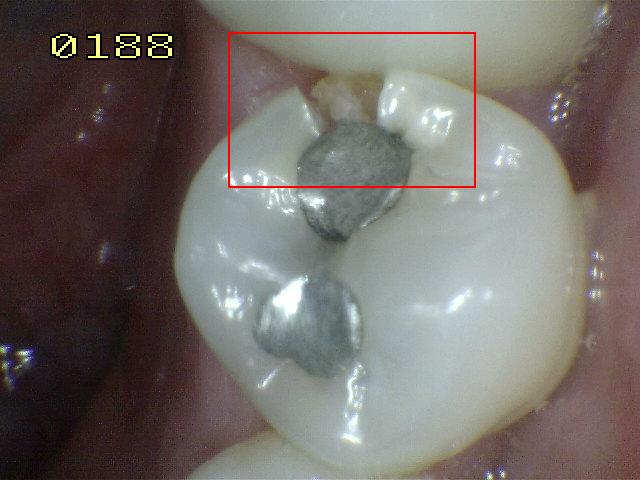

Código 4

(Caries Moderada): Sombra oscura

de dentina subyacente al esmalte intacto con o sin interrupción

localizada del esmalte

- La superficie de los dientes

puede tener características de código 2 y tiene una

sombra de dentina con cambio de color que es visible a

través de una superficie de esmalte aparentemente

intacto o con ruptura localizada en el esmalte pero sin

dentina visible. Este aspecto se ve más fácilmente

cuando el diente está húmedo y es una sombra oscura e

intrínseca que puede ser de color gris, azul, naranja o

café.

- Nota: observar el diente húmedo y luego seco. Esta

lesión debe distinguirse de sombras ocasionadas por

amalgama.